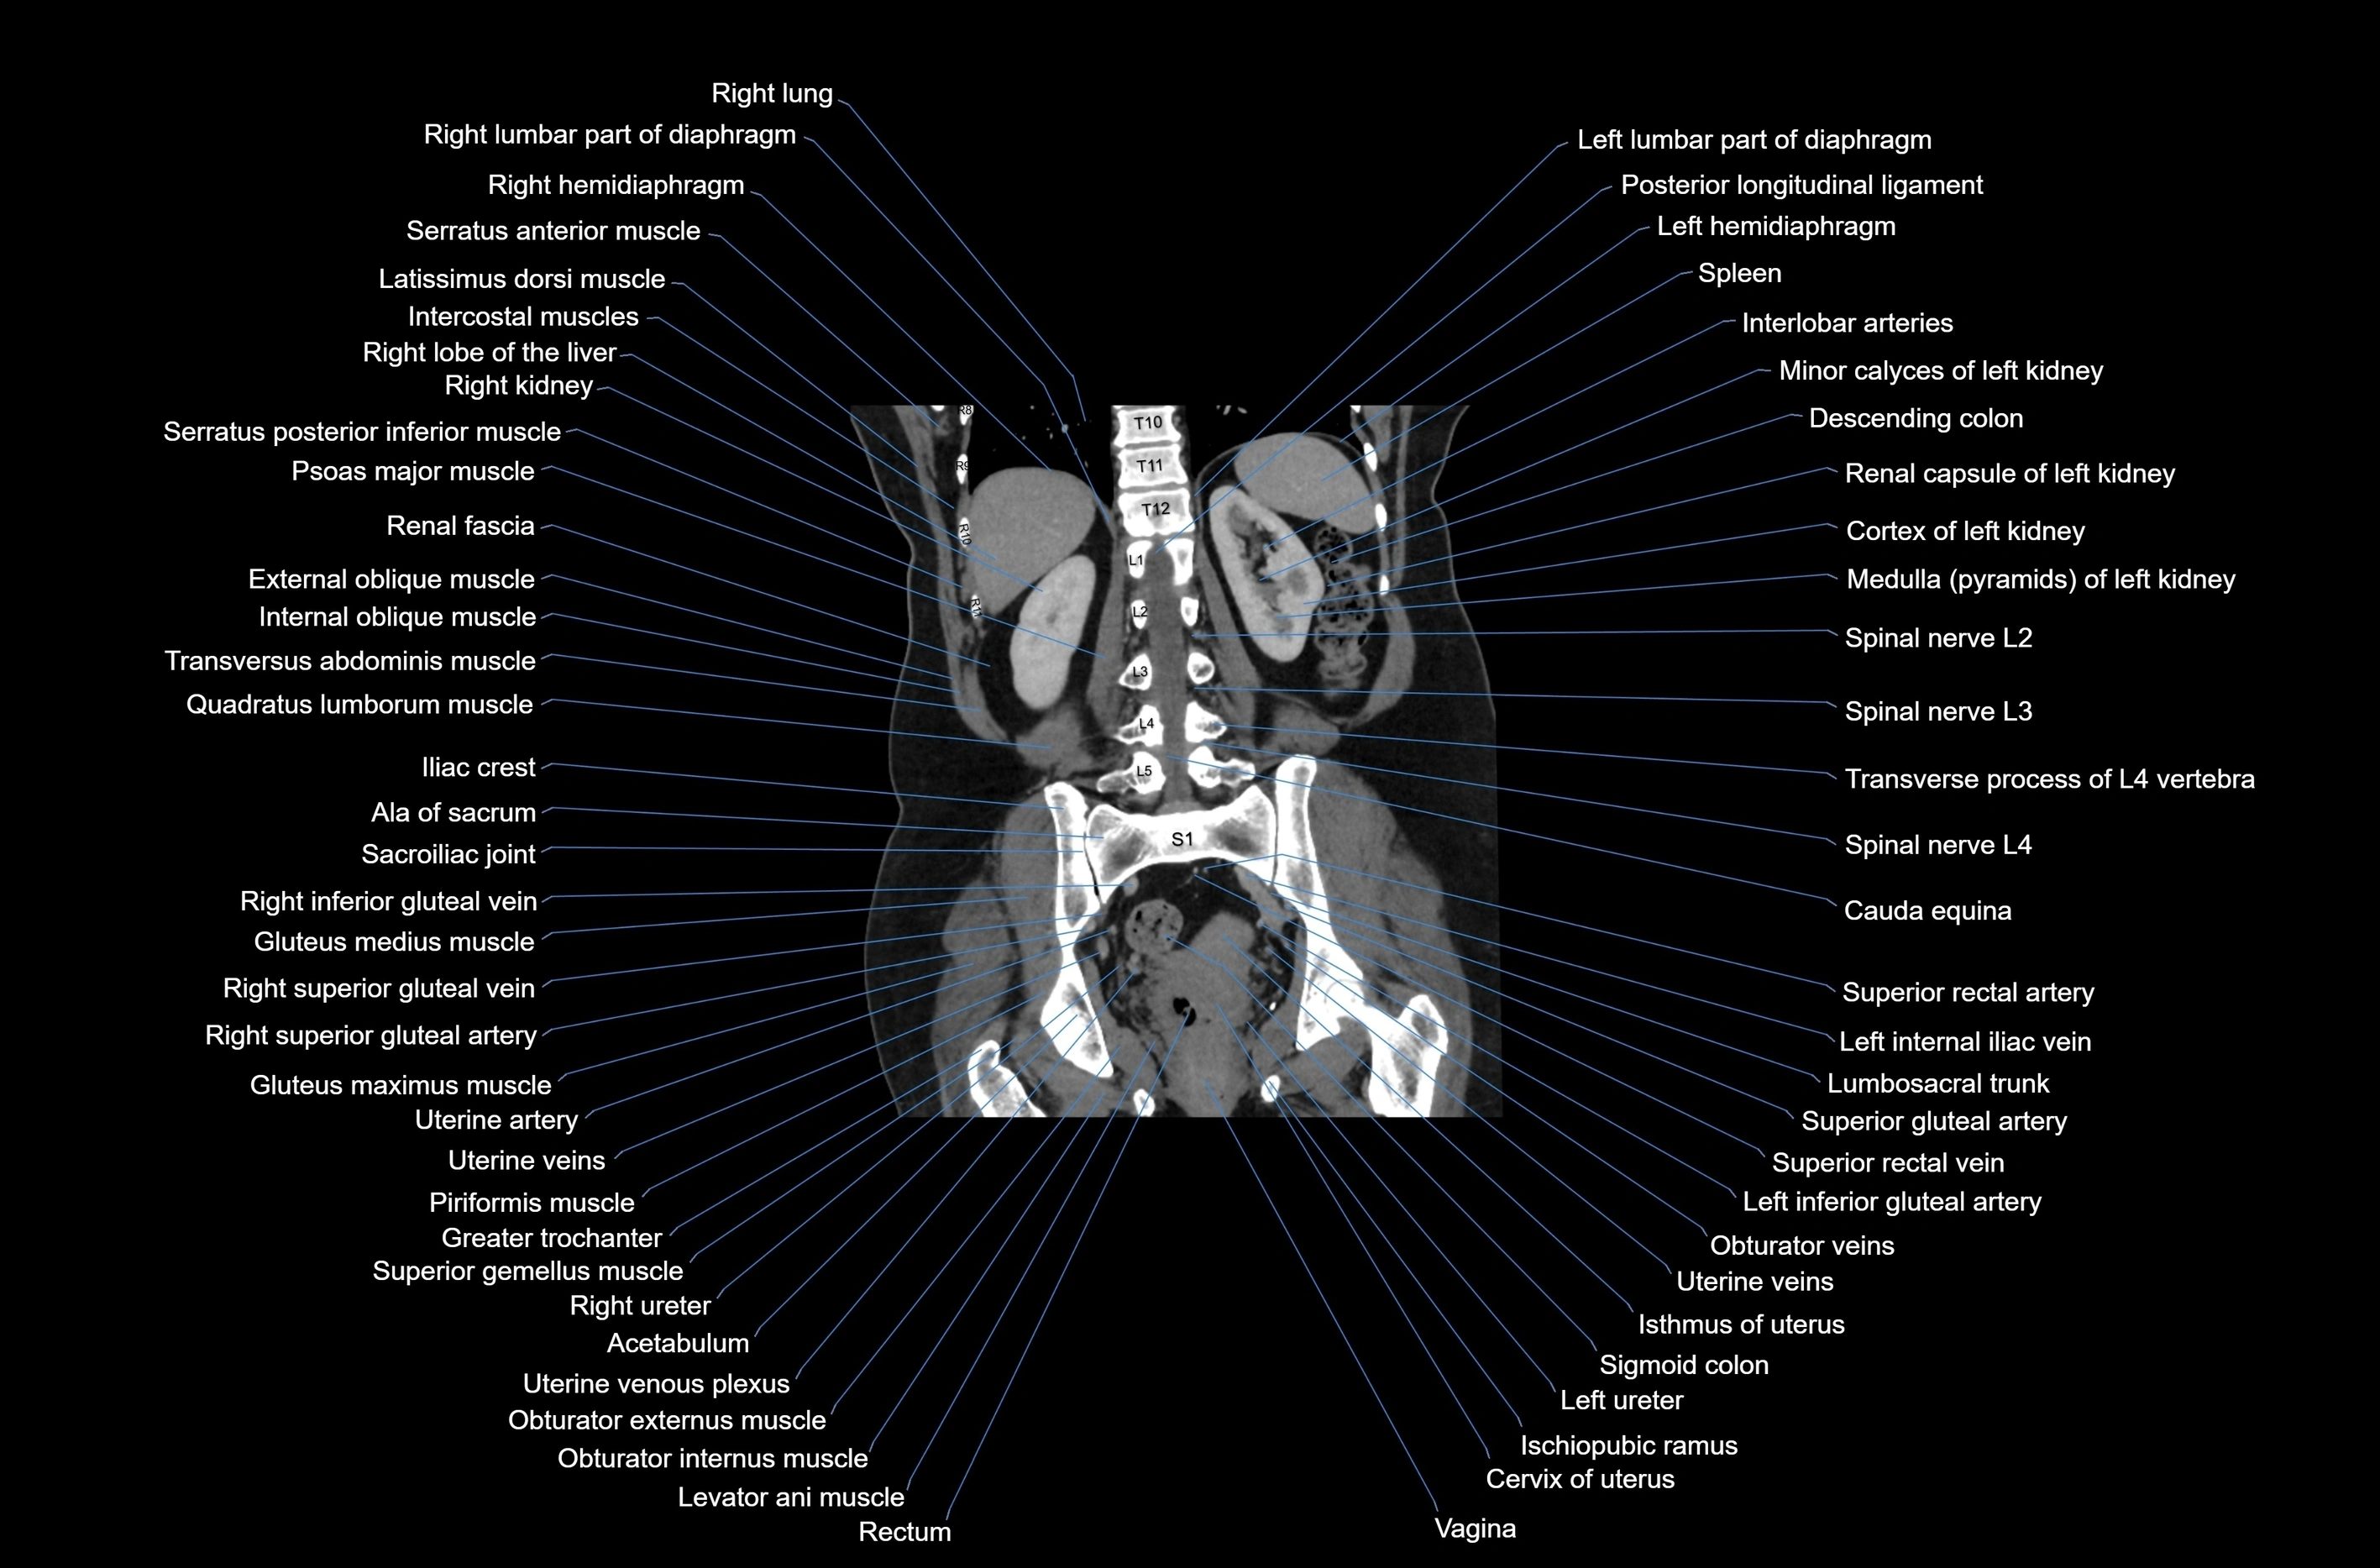

CT images